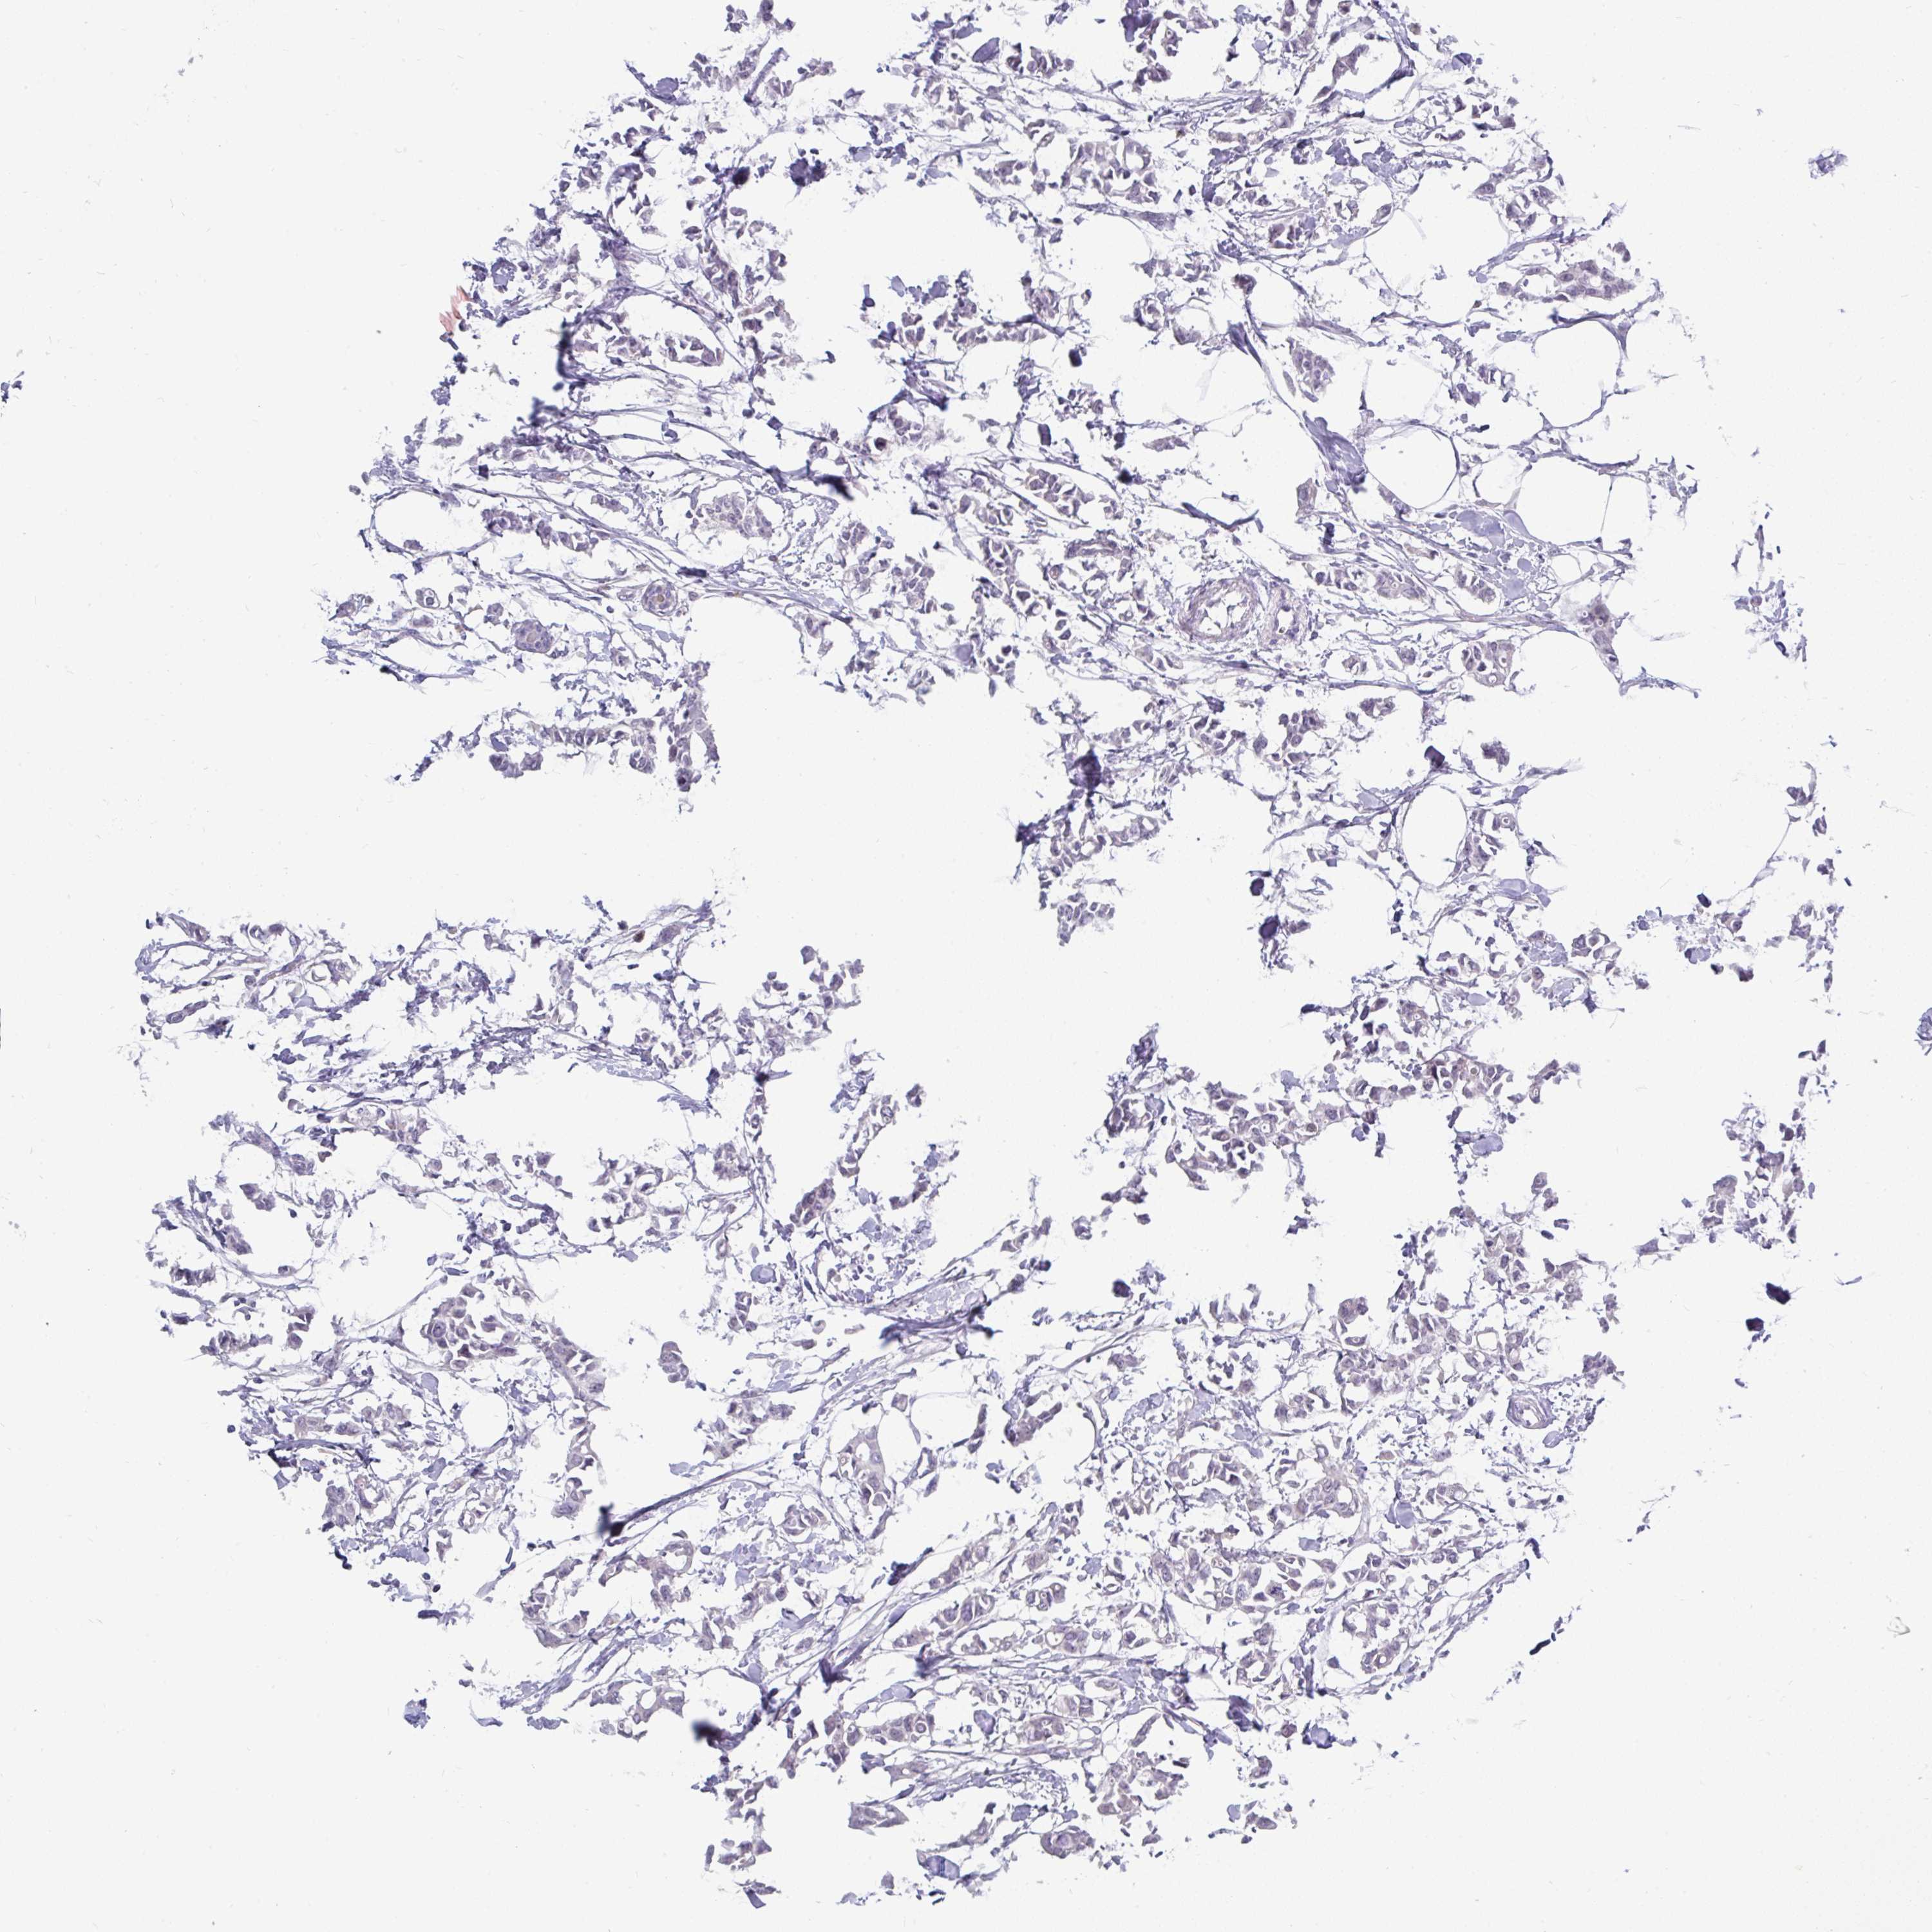

CANCER BREAST CANCER Show tissue menu

Breast cancer

Human cancer

INTS5 is not prognostic in Breast Invasive Carcinoma (TCGA)